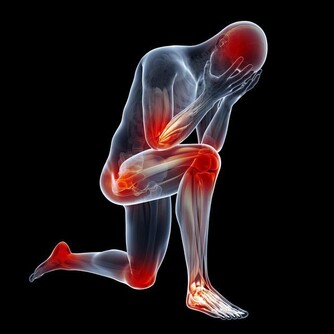

4.也許你將是一隻斷翅的天使

如果你是甲狀腺癌淋巴轉移的患者,這種後遺症就十之八九會發生在你身上。因為手術中會給你進行淋巴清掃,而這個過程,先要斷掉你的一側的相關肌肉。我就是斷了左側的胸鎖乳突肌和斜拉三角肌。所以,術後的左側胳膊,就出現了一些活動困難的情況。凡是生活中涉及到這兩塊肌肉用力時,都是使不上勁的。

如果把正常人的胳膊和身體看做是連接很好的軸承,那手術後的胳膊就像是軸承壞了,用一根繩子代替連在身體上。平時看著也挺好,等到需要用力抬高時,軸承上去了,繩子卻下來了。我的很病友都出現這種情況了。醫生也會在手術後醫囑讓我們多活動這一側的肌肉。你說這個樣子像不像斷翅的天使?